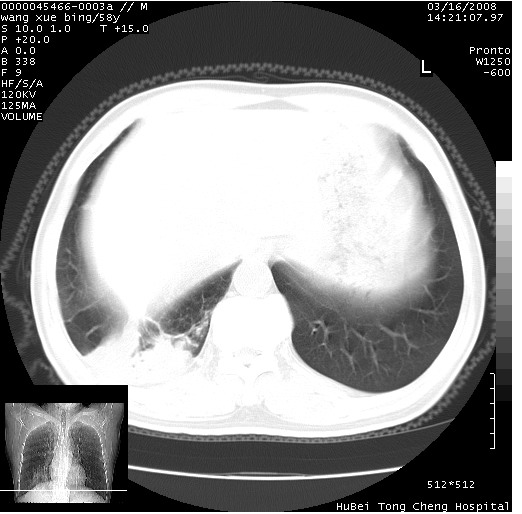

患者 男,58岁。咳嗽、咯血3月余。

胸部cr x线片提示:1)右下肺脓肿。2)右下肺周围型肺癌不排除。建议:行ct扫描检查。

胸部ct轴位平扫(层厚10mm,螺距1.5,重建间隔10mm),图像如下:

右肺下叶见不规则厚壁空洞,内壁不规则,外缘见粗长毛刺,临近胸膜明显增厚并与病灶关系密切。支持考虑:周围型肺癌!

右肺下叶周围型肺癌伴空洞形成!征象比较明显!分叶、毛刺、胸膜凹陷征、厚壁空洞,壁结节!

影像符合癌性空洞表现,临床如无咳大量浓臭痰史,还是考虑周围型肺癌可能性大。

空洞壁厚,不规则,其内可见壁结节,周围可见毛刺及阻塞性炎变,多考虑癌性病变.

空洞内壁不规整,有壁结节,周围有毛刺,支持癌性空洞。